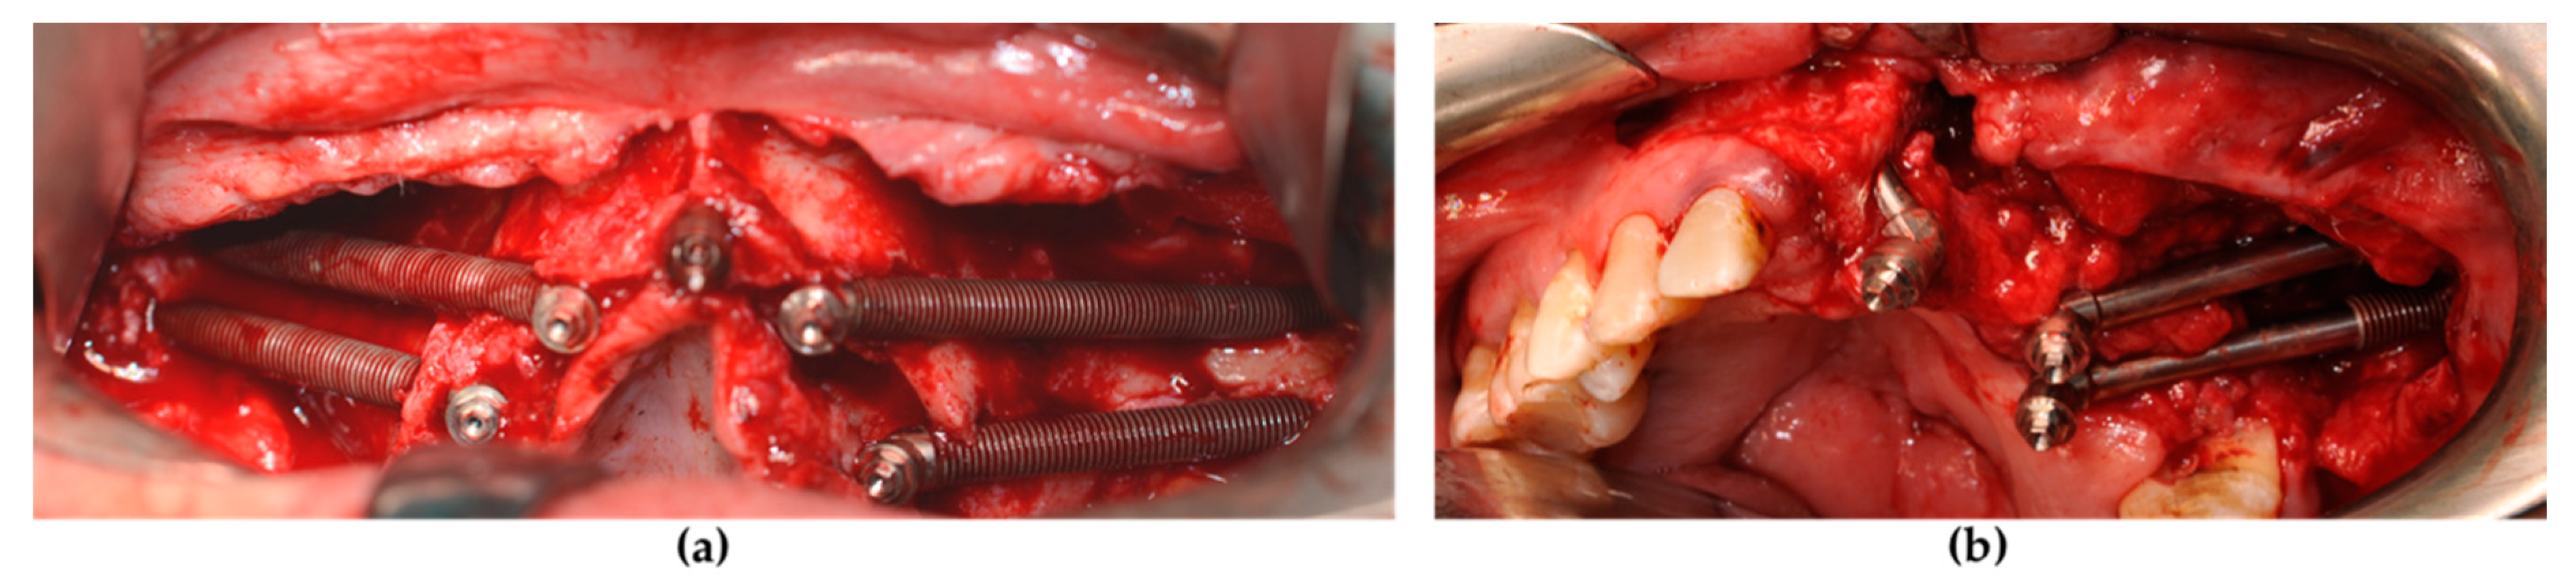

Figure 2. The zygomatic implant was placed and the conical abutment was screwed before suturing. (a) The standard type of zygomatic implant was used for patients with maxillary atrophy. (b) An oncologic type of zygomatic implant with a machined coronal part was used for implant sites that lacked crestal bone.

A maxillofacial type navigation system involving the use of an extraoral reference tool (onto the cranial bone) was employed in three oncologic patients in whom the residual maxillary bone was not sufficient for the fixing of the intraoral reference tool. After a final evaluation carried out by a depth gauge, zygomatic implants (Southern Implants, Irene, South Africa) were positioned via the use of implant motor or manually using a fixture mount. Standard zygomatic implants were placed in patients from the atrophic group and in oncologic patients when the implant collar was surrounded by the residual crestal bone (Figure 2a). The oncologic type of zygomatic implant was placed when there was only soft tissue around the implant collar (Figure 2b).

All oncologic patients underwent an oral-antral/nasal primary closure at least with soft tissue. The conical abutment was screwed onto each implant at a torque of 25 NCm using a dynamometric wrench. Finally, the impression transfers were positioned and the flap was sutured (Vicryl 4-0, Ethicon, Somerville, MA, USA).